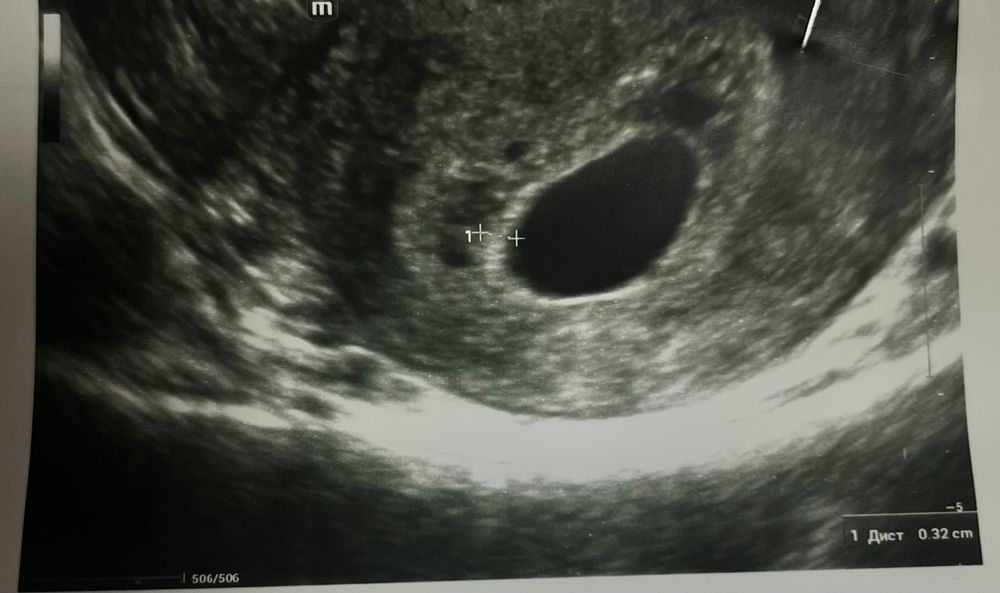

Анэмбриония почему

Анэмбриония почему 116 фотографий